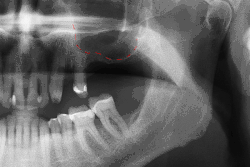

Before undergoing sinus augmentation, diagnostic tests are used to determine the health of the patient's sinuses. Panoramic radiographs are taken to map out the patient's upper jaw and sinuses. In special instances, cone beam computed tomography is preferable in measuring sinus height and width, ruling out any sinus disease or pathology.[7]